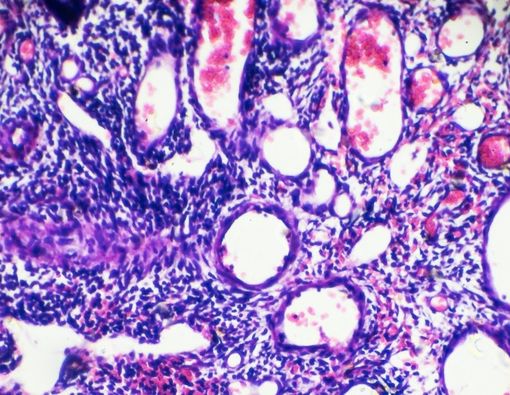

Polip serviks memiliki warna berbeda, seperti abu-abu, putih, ungu atau bahkan merah terang. Polip yang bisa berkembang di leher rahim ada dua jenis, yaitu:

- Polip ektoserviks, di mana sel-sel tumbuh di luar serviks. Polip ini cenderung dialami oleh wanita yang sudah menopause.

- Polip endoserviks, yang pertumbuhan sel-selnya berada di dalam serviks. Polip endoserviks umumnya dialami oleh wanita yang mengalami premenopause.

Pada saat pemeriksaan, dokter dapat melihat jaringan halus di leher rahim yang berwarna kemerahan atau ungu.

Jika dicurigai ada tanda keberadaan polip serviks, dokter dapat melakukan biopsi yang dilanjutkan dengan pemeriksaan laboratorium.

Biasanya hasil pemeriksaan laboratorium dapat menunjukkan apakah sel polip tersebut jinak atau tidak.